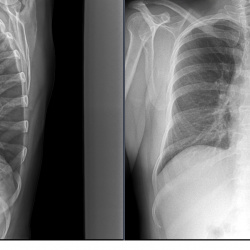

Здравствуйте, девочка 18 лет жалоб нет, в верхней доле слева видится тень, досняли с поднятыми руками вроде сохраняется. Что скажете норма или лучше в динамике посмотреть?